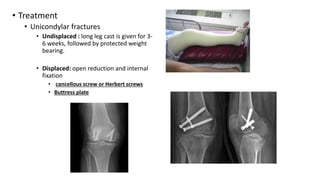

• Treatment

• Unicondylar fractures

• Undisplaced : long leg cast is given for 3-

6 weeks, followed by protected weight

bearing.

• Displaced: open reduction and internal

fixation

• cancellous screw or Herbert screws

• Buttress plate